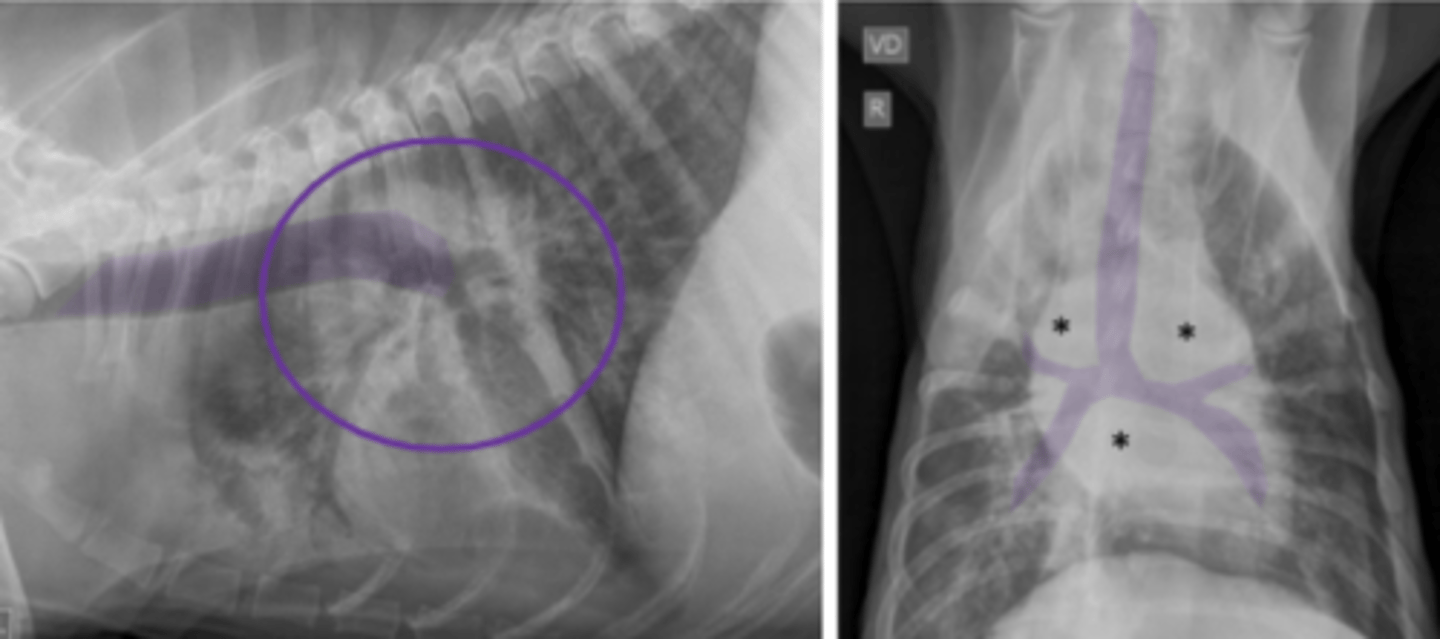

conducto arterioso patente

(cardiomegalia izq, regiones engrosadas- arco aortico, arteria pulmonar, auriculo izq)

patología:

estenosis pulmonar

(cardiomegalia derecha, arteria pulmonar engrosada)